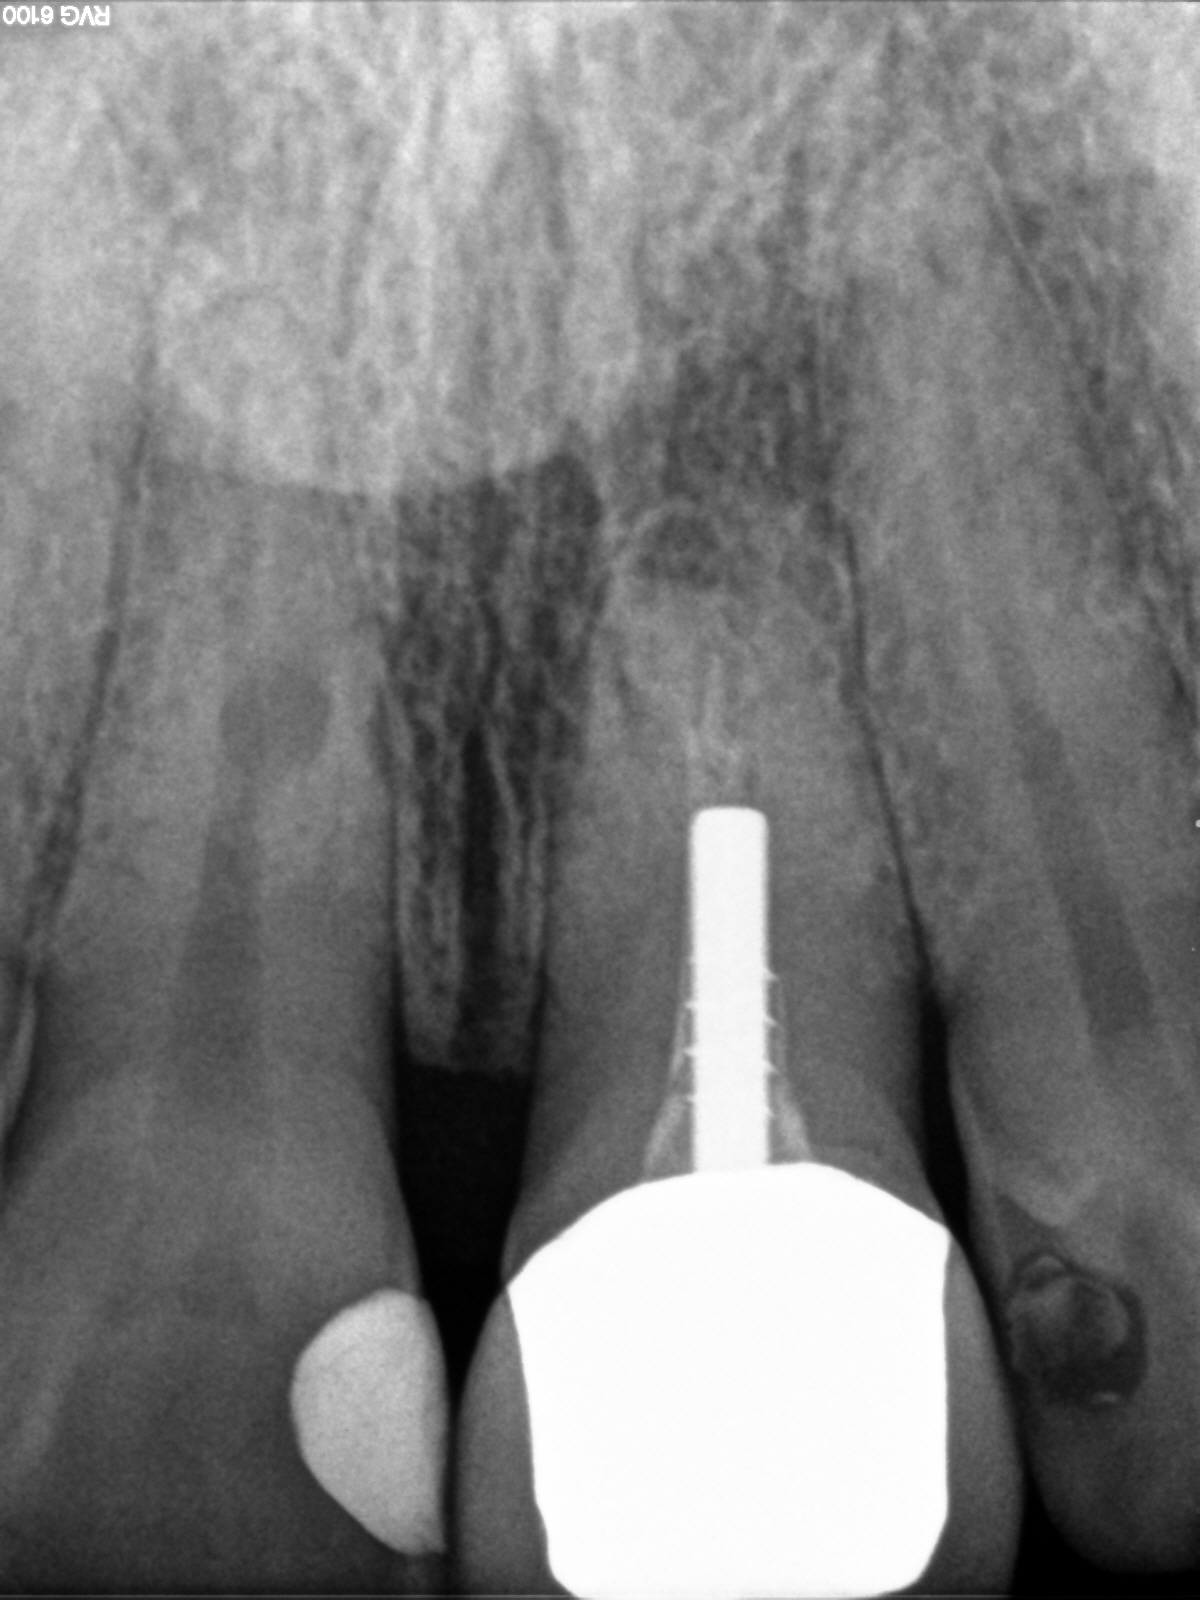

11 Verdacht auf iatrogene Beschädigung der Zahnwurzel, kreisrunde, scharf abgegrenzte, weichteildichte Aufhellung im mittleren Wurzeldrittel, Pulpahohlraumbegrenzung nach mesial ist erhalten, daher kein Verdacht auf interne Resorption.

Jörg, da bist Du schon ganz dicht dran. Es geht um den Befund am Zahn 11 nicht im Zahn 11. Bei genauer Betrachtung sieht man die Kontur des Wurzelkanals.

11: Kreisrunde Transluzens im mittleren Wurzeldrittel. Die Verdachstdiagnose von Jörg ist sehr interessant. Hätte ich nicht vermutet, ist aber durchaus möglich zumal auch von mesial ein kleiner Defekt mit minderer Dichte zu erkennen ist. Ist mir aber für iatrogen etwas zu weit krestal gelegen.

21: Zustand nach WSR ist offensichtlich, der unvollständige, inhomogene WF stimme ich vollumfänglich zu, die periapikale Situation zeigt wolkige Strukturen minderer Dichte, IMO eine akute Reinfektion mit resorptiven Prozessen.

21 Zustand nach WSR, unvollständige, inhomogene WF, fehlender retrograder Verschluss, unklare periapikale Situation